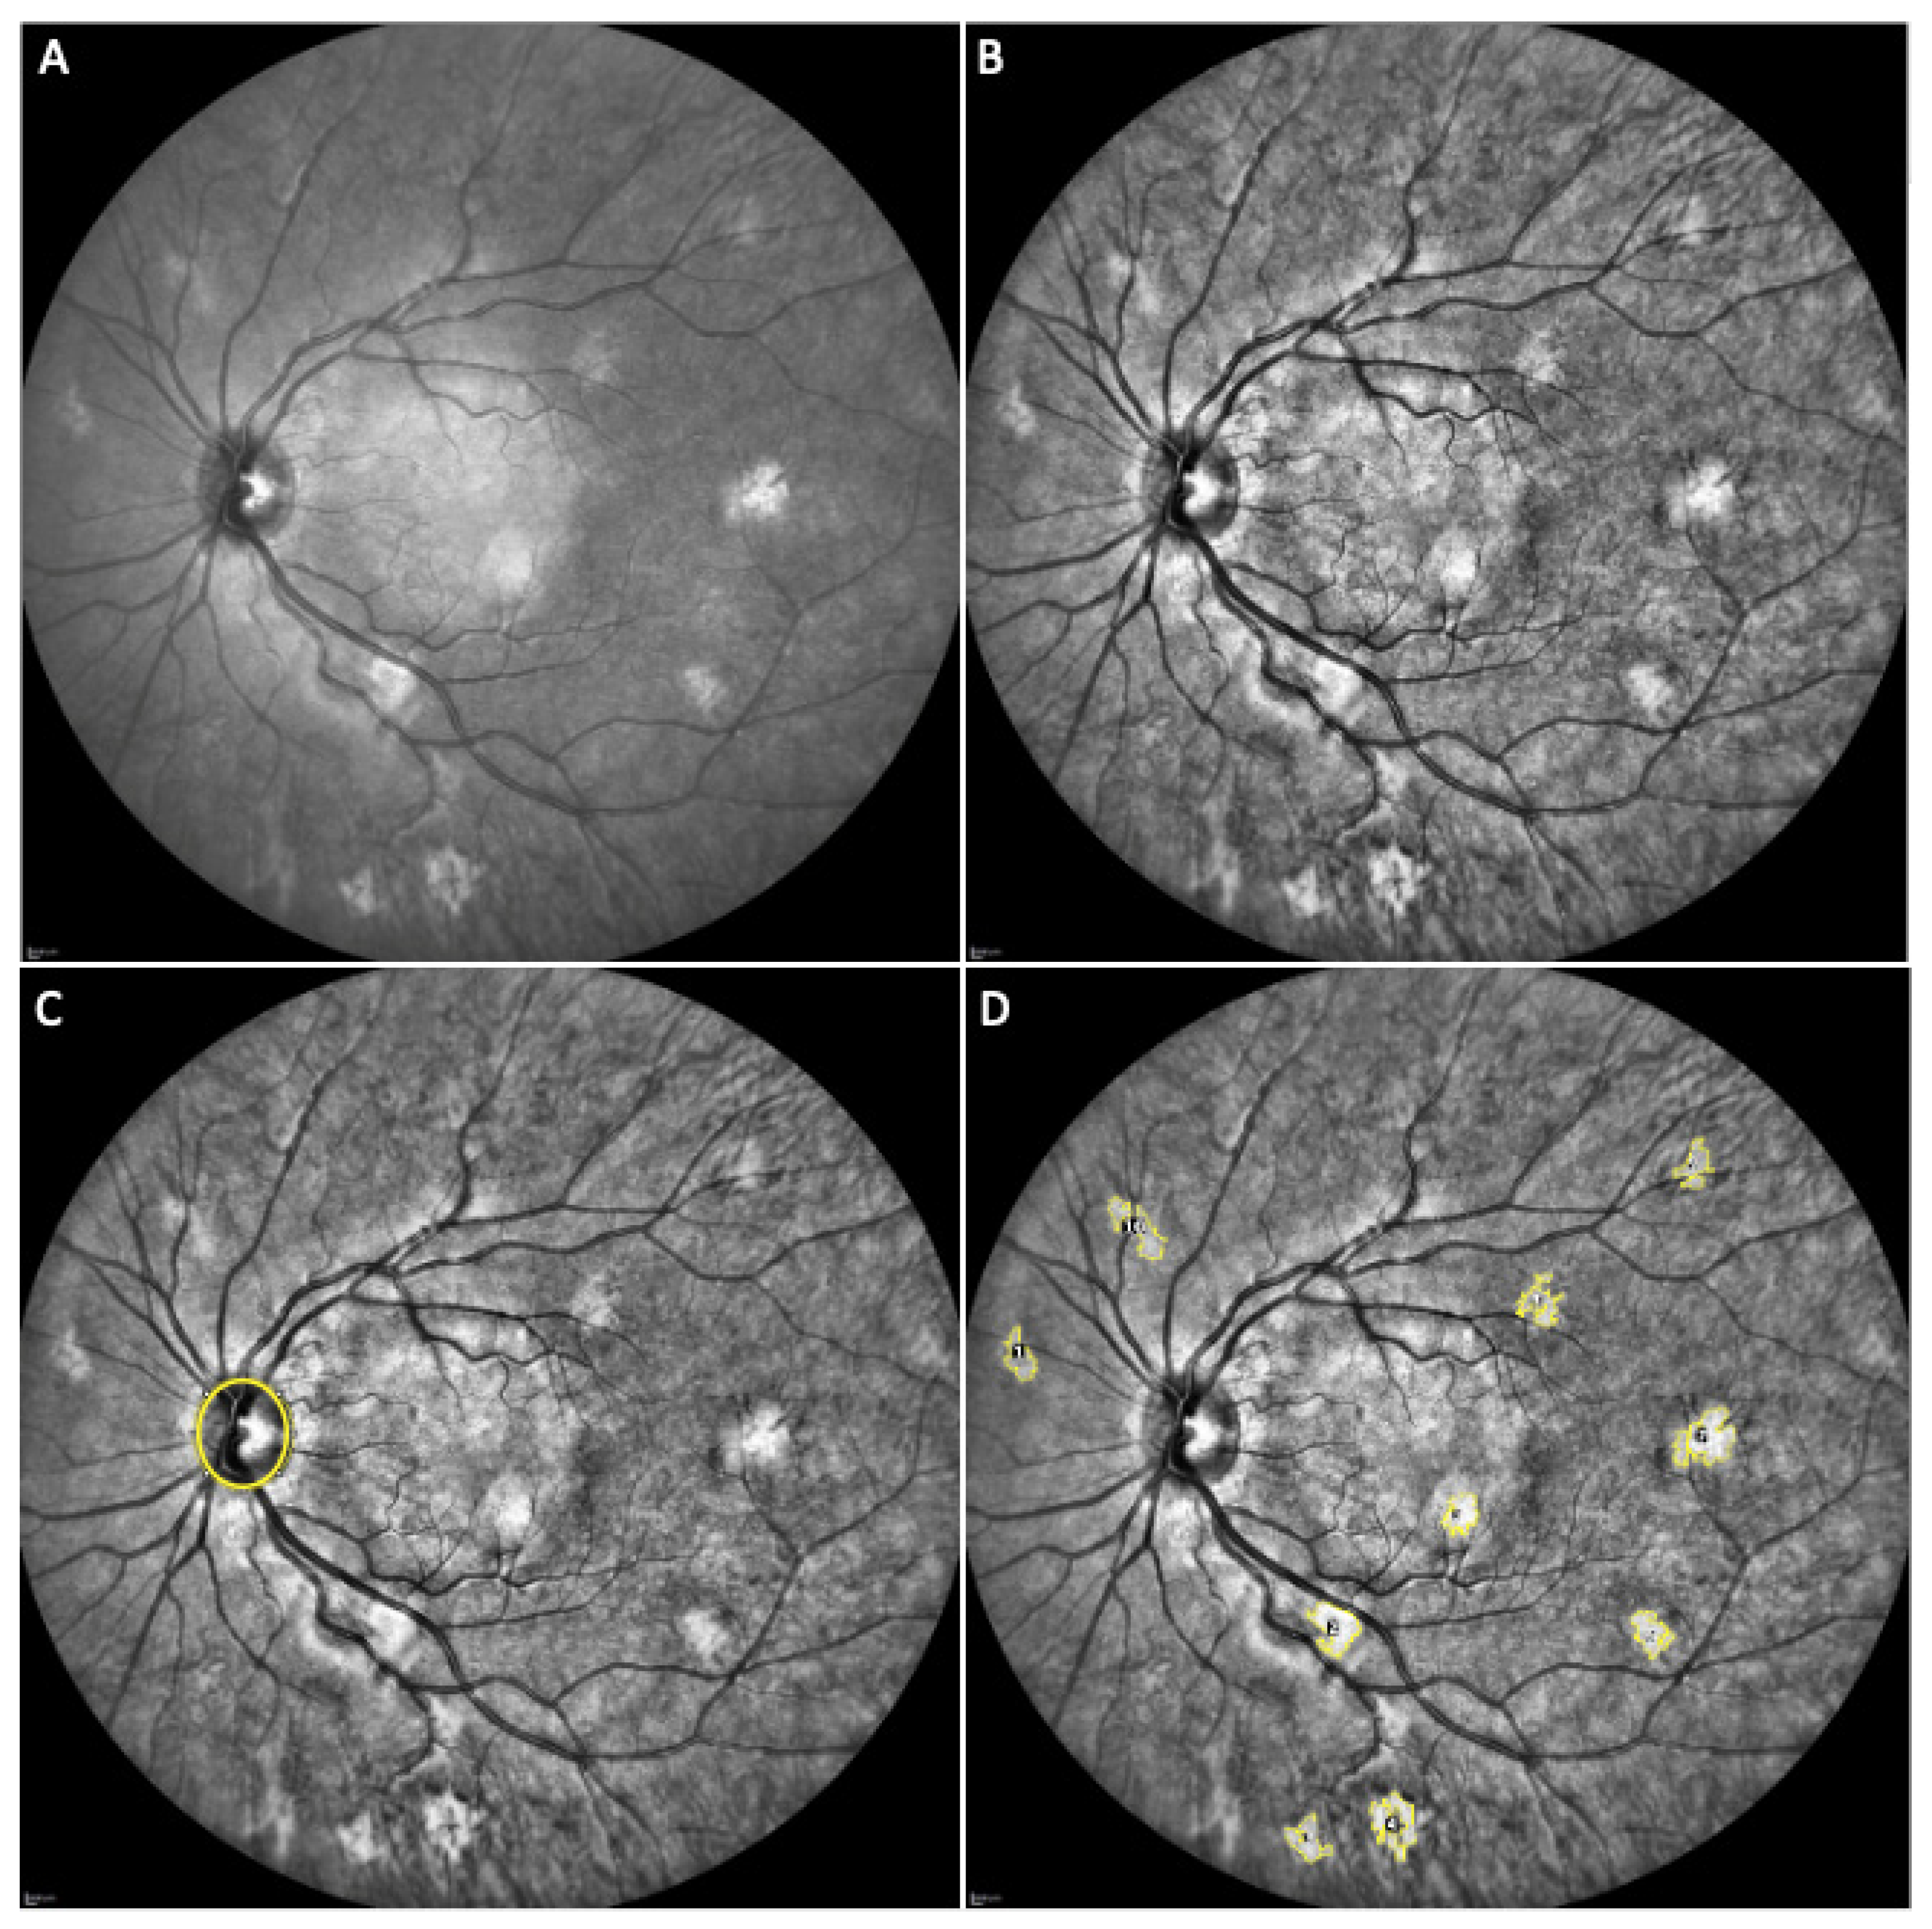

- Parrozzani, R.; Clementi, M.; Frizziero, L.; Miglionico, G.; Perrini, P.; Cavarzeran, F.; Kotsafti, O.; Comacchio, F.; Trevisson, E.; Convento, E.; et al. In vivo detection of Choroidal abnormalities related to NF1: Feasibility and comparison with standard NIH diagnostic criteria in pediatric patients. Investig. Ophthalmol. Vis. Sci. 2015, 56, 6036–6042. [Google Scholar] [CrossRef]

- Vagge, A.; Camicione, P.; Capris, C.; Sburlati, C.; Panarello, S.; Calevo, M.G.; Traverso, C.E.; Capris, P. Choroidal abnormalities in neurofibromatosis type 1 detected by near-infrared reflectance imaging in paediatric population. Acta Ophthalmol. 2015, 93, e667–e671. [Google Scholar] [CrossRef]

- Viola, F.; Villani, E.; Natacci, F.; Selicorni, A.; Melloni, G.; Vezzola, D.; Barteselli, G.; Mapelli, C.; Pirondini, C.; Ratiglia, R. Choroidal abnormalities detected by near-infrared reflectance imaging as a new diagnostic criterion for neurofibromatosis 1. Ophthalmology 2012, 119, 369–375. [Google Scholar] [CrossRef] [PubMed] [Green Version]

- Yasunari, T.; Shiraki, K.; Hattori, H.; Miki, T. Frequency of choroidal abnormalities in neurofibromatosis type 1. Lancet 2000, 356, 988–992. [Google Scholar] [CrossRef]

- Nakakura, S.; Shiraki, K.; Yasunari, T.; Hayashi, Y.; Ataka, S.; Kohno, T. Quantification and anatomic distribution of choroidal abnormalities in patients with type I neurofibromatosis. Graefe’s Arch. Clin. Exp. Ophthalmol. 2005, 243, 980–984. [Google Scholar] [CrossRef]

| Number (mean ± sd) | 3.6 ± 3.2 | 4.6 ± 3.5 | 6.4 ± 4.1 | 8.1 ± 4.8 | 9.6 ± 5.3 |

| Area 1 (mean ± sd) | 1.159 ± 0.975 | 1.367 ± 1.178 | 1.495 ± 1.162 | 1.534 ± 1.213 | 2.130 ± 1.564 |

| Perimeter 2 (mean ± sd) | 4.858 ± 3.745 | 5.320 ± 4.417 | 5.753 ± 4.652 | 5.803 ± 4.647 | 6.956 ± 4.536 |